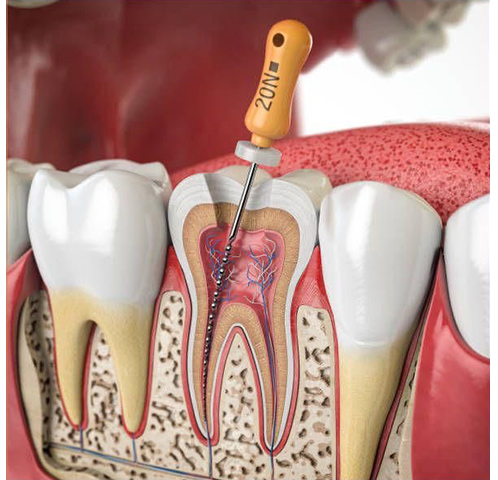

Лікування періодонтиту є комплексним процесом, спрямованим на ліквідацію інфекції в кореневих каналах, відновлення функції зуба та попередження рецидиву захворювання. У нашій клініці професійна терапія проводиться за чітким протоколом, що включає такі етапи:

- Отримання доступу до кореневих каналів. Лікар розсвердлює коронку зуба, видаляє старі пломби та всі уражені карієсом тканини, щоб відкрити вхід до каналів.

- Механічна та медикаментозна обробка каналів. За допомогою спеціальних ендодонтичних інструментів стоматолог ретельно видаляє інфіковану пульпу, розширює та формує канали. Паралельно вони промиваються потужними антисептичними розчинами для повної дезінфекції.